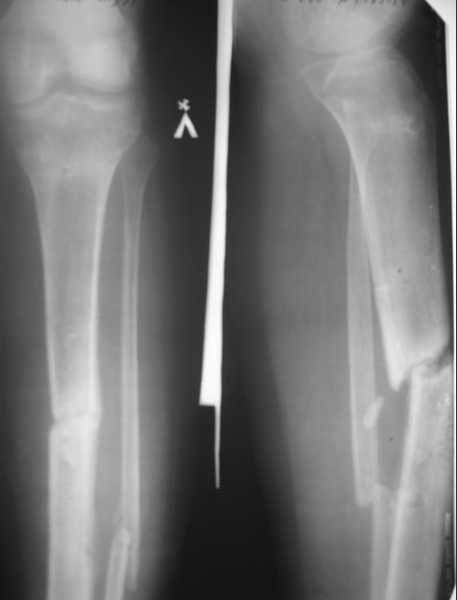

Ложный сустав большеберцовой кости. |

пациент 20 лет, травма в июне 2007 г. Открытый перелом костей левой голени со смещением отломков. В этот же день выполнена ПХО открытого перелома костей левой голени, фиксация в КДА по Илизарову. Раны заживали вторичным натяжением. В январе 2008г. сняли аппарат, по причине нестабильности, - гипсовая иммобилизация. На данный момент согласно контрольным рентгенограммам и времени прошедшего с момента травмы имеется нормо, гипотрофичный ложный сустав большеберцовой кости. Местно - признаков воспаления не определяется. Лабораторные показатели в пределах нормы.

1. Рассверлить канал риммерами до диметра 12 – 13 мм, и выполнить остеосинтез блокированным канюлированным стержнем диметром 11 – 12 мм.

1. Достаточно ли для стимуляции остеогенеза только рассверливания костно – мозгового канала, есть ли необходимость в костной пластике и декортикации, нужно ли выполнить остеотомию малоберцовой кости?